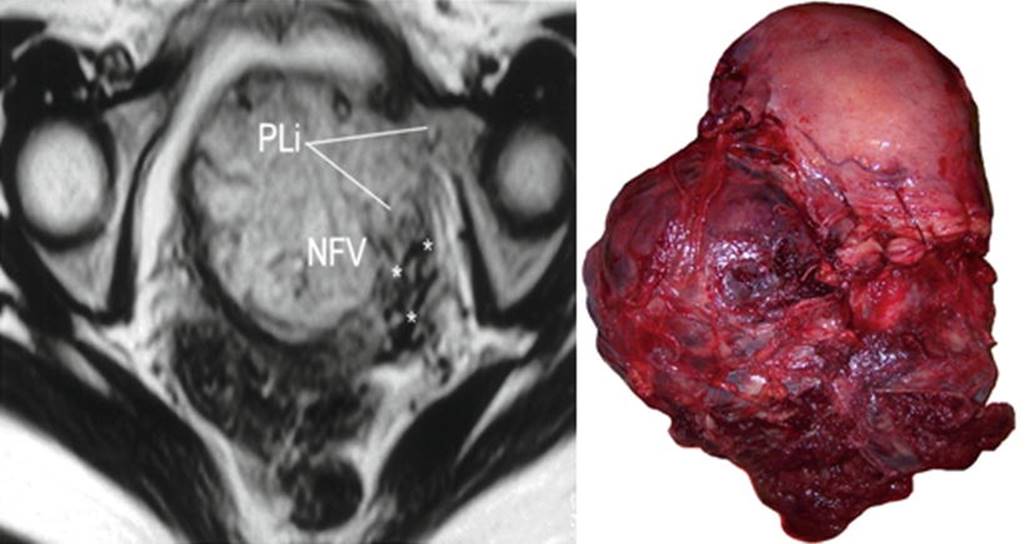

Fig. 14.8

Left: axial T2 image, PLi parametrial invasion, NFV newly formed vessels (asterisks). Right: massive low parametrial invasion. Uterine segment was not invaded by the placenta. MRI was requested by US doubt of anterior invasion